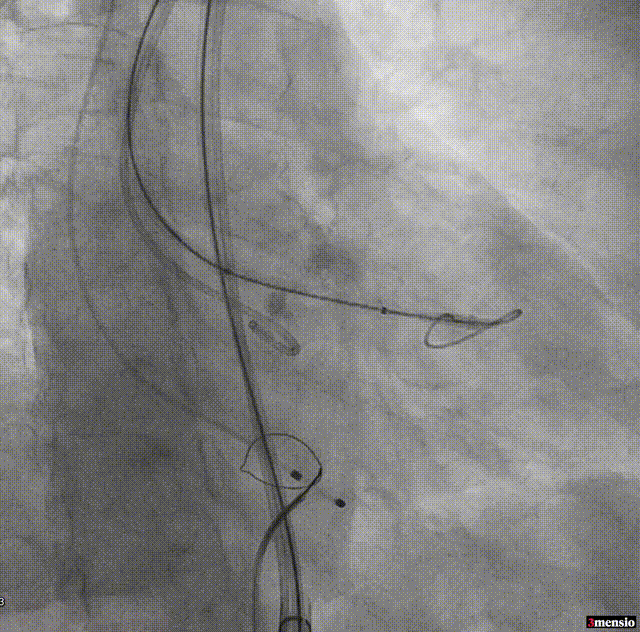

18mm球囊预扩

95/05定位

MuguetA™21 mm瓣膜+1cc释放

释放后腰迹明显,轻度瓣周漏,原体积后扩

根部造影显示微量瓣周漏